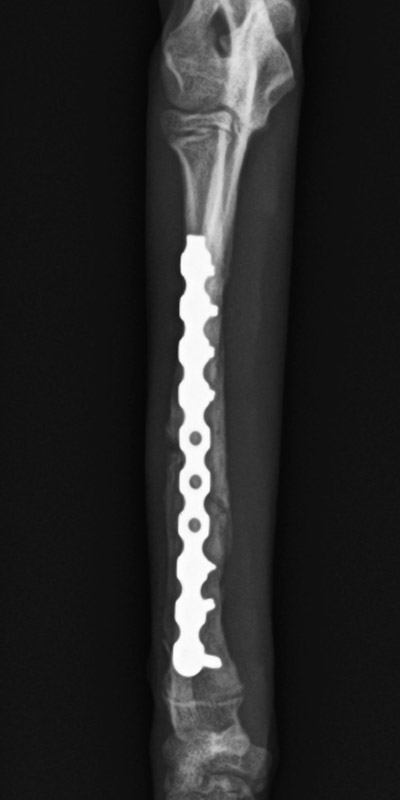

橈尺骨骨折

トイプードル(8カ月齢)

ボール運動中に転倒

手術後